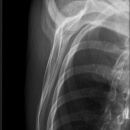

Schulter axial

Beurteilungskriterien